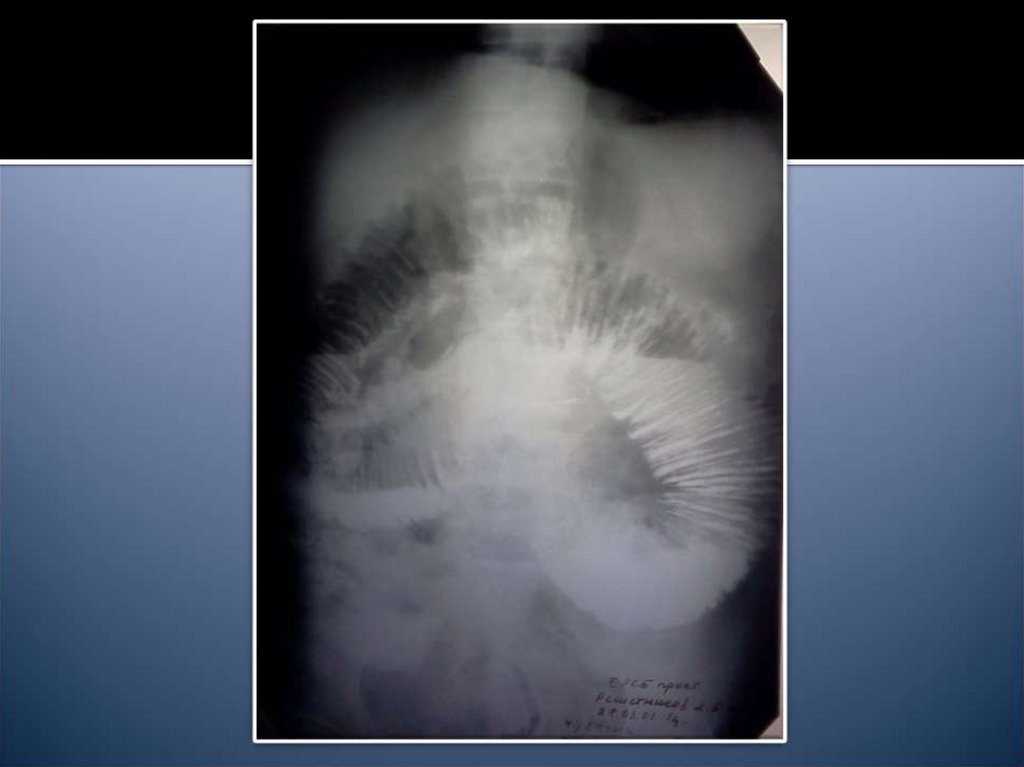

14. Рентгенологические признаки

Чаши Клойбера

Симптом Кивуля (аркады)

Проба Шварца

Пневматоз петель кишечника